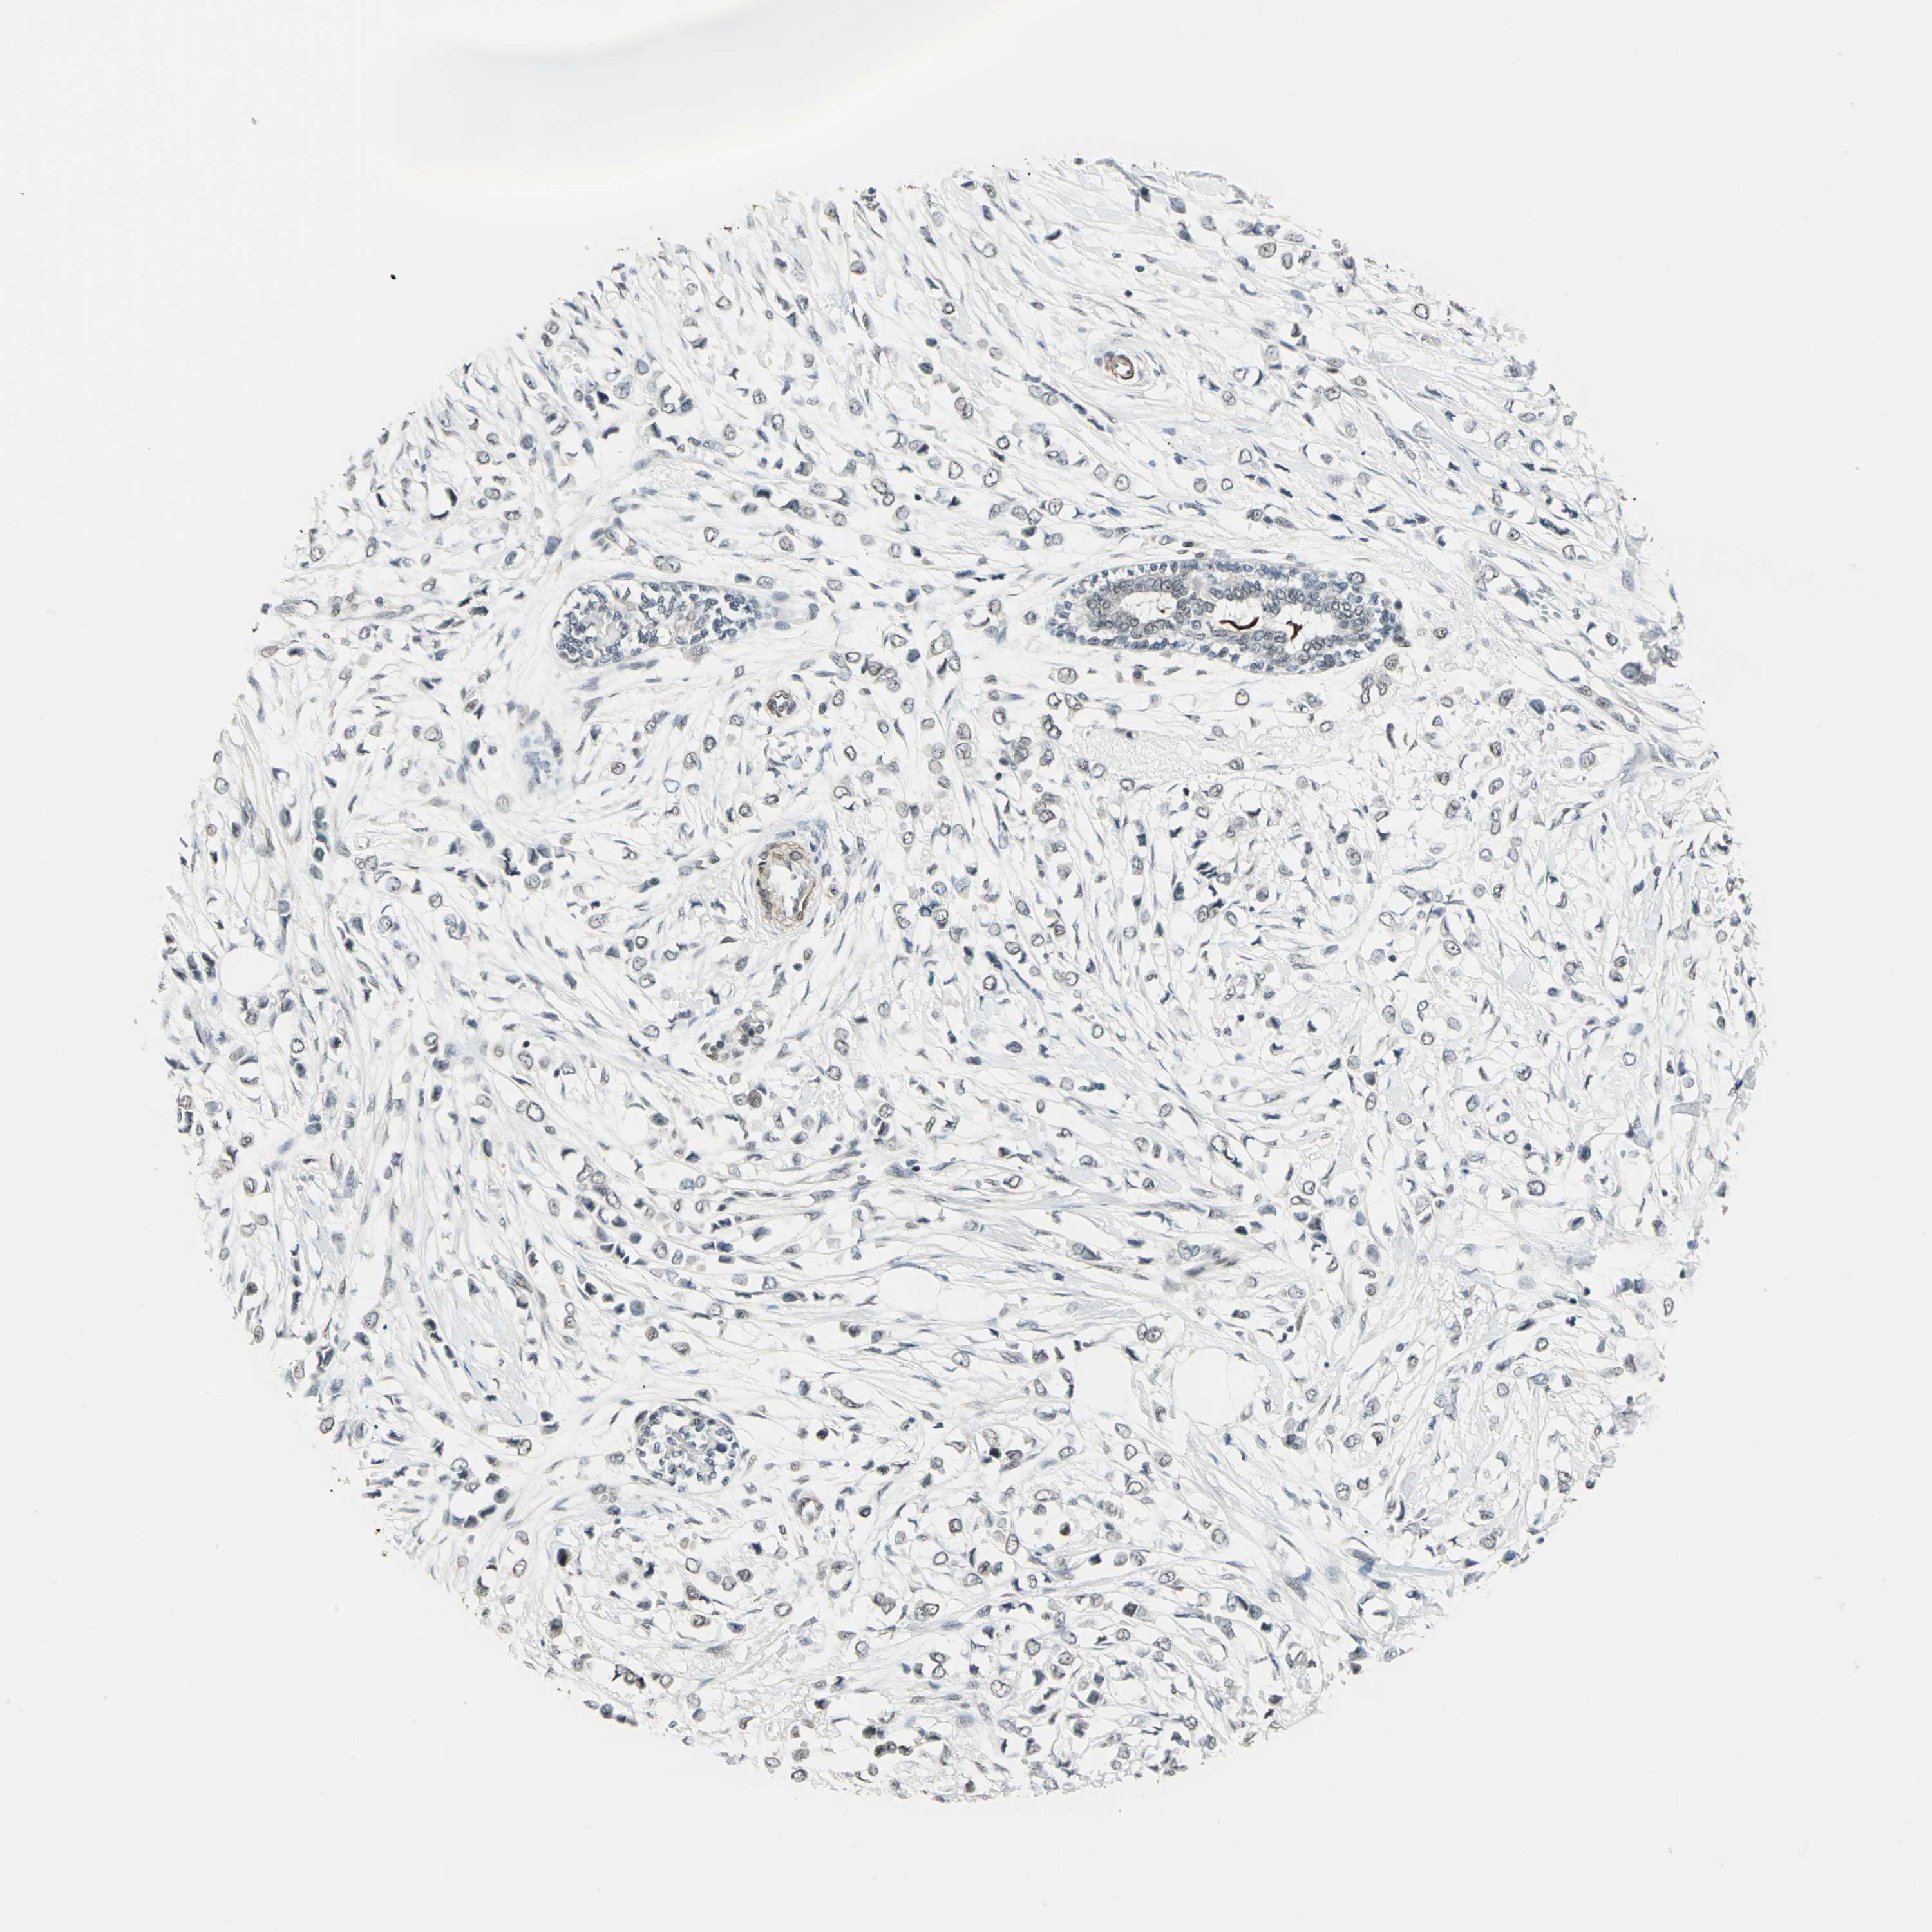

BRCA TCGA BRCA VALIDATION PROTEIN EXPRESSION